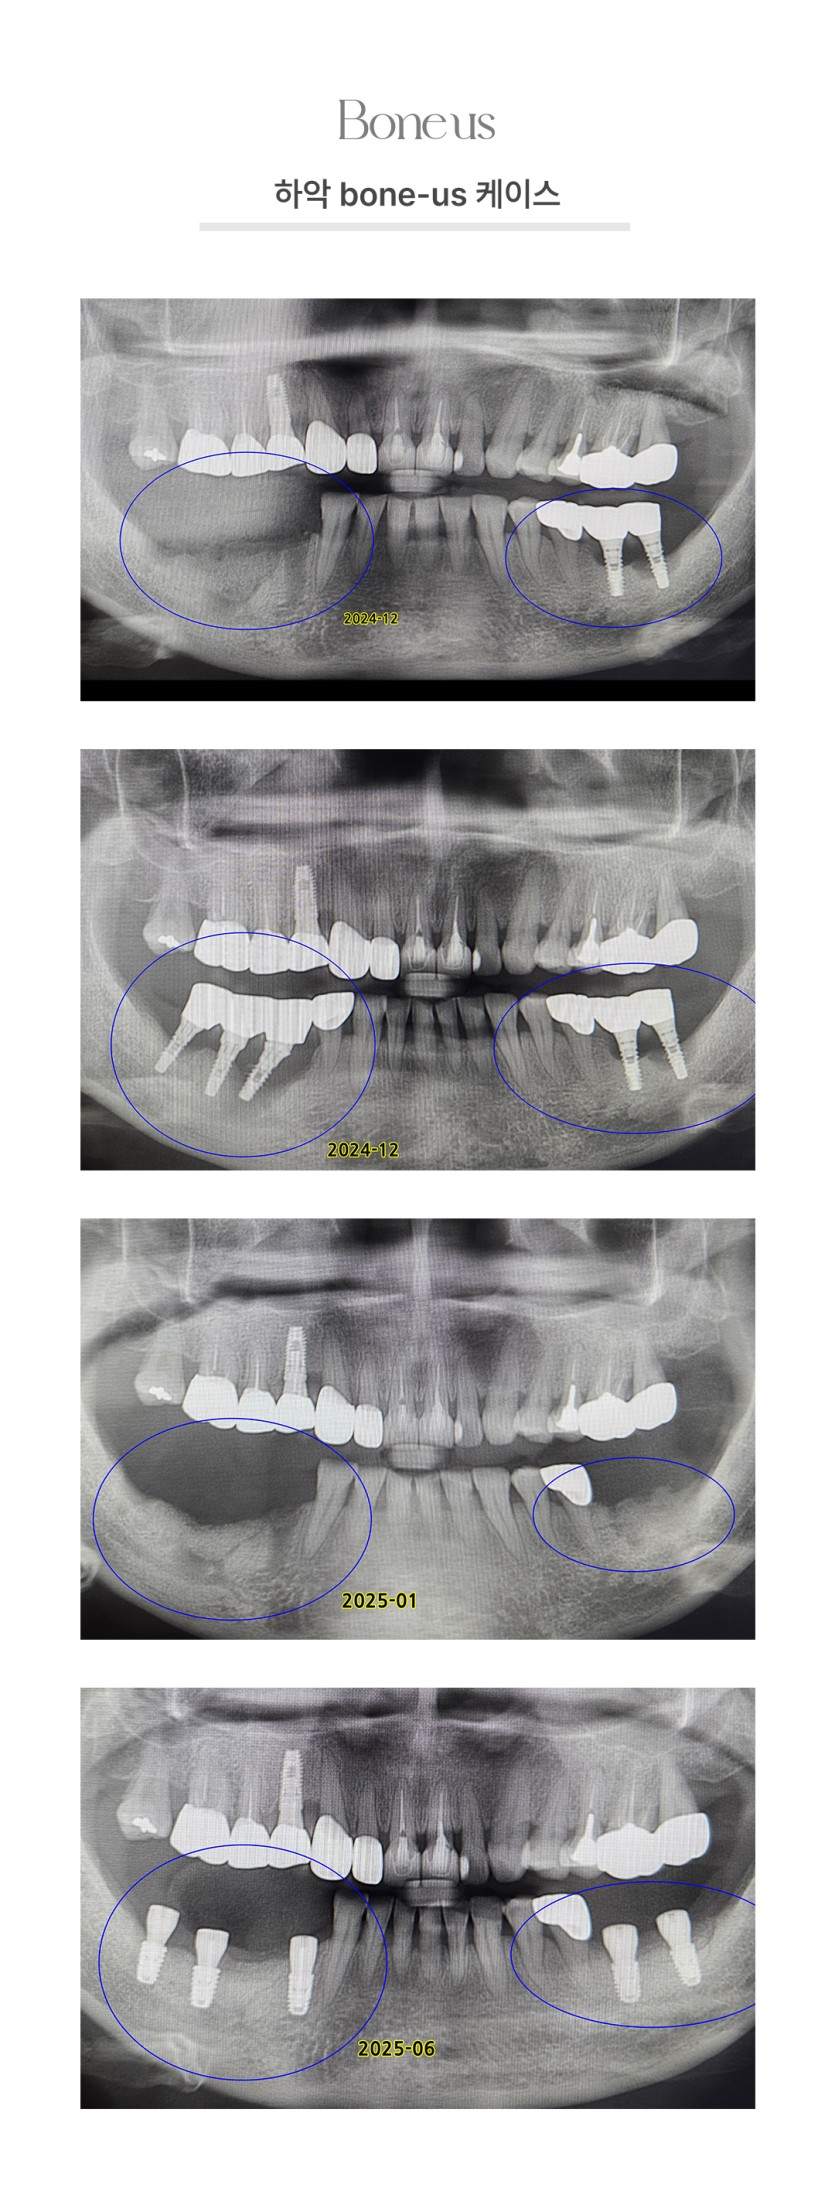

하악 본어스 케이스 3